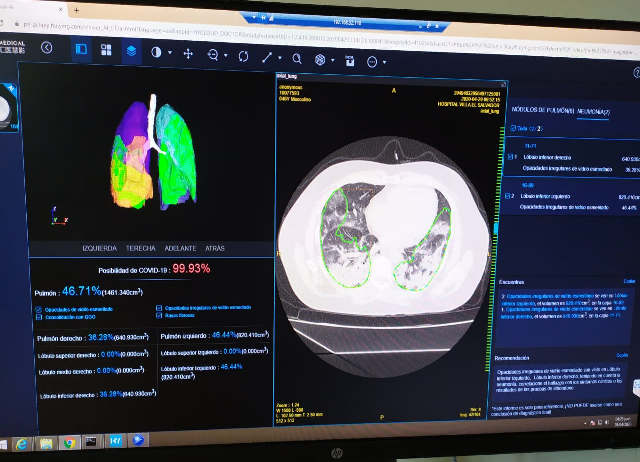

De este modo podrán realizar una detección máximo en 30 segundos y puede distinguir entre neumonía y la Nueva Neumonía por Coronavirus (NCP por sus siglas en inglés), luego coloca los contornos sospechosos de neumonía de las tomografías computarizadas, y los mide y clasifica con precisión; posterior, todos los datos son analizados bajo la solución de IA (Inteligencia Artificial) en la nube pública de Huawei (Huawei Cloud), para compararlos con diferentes estudios y realizar verificaciones de cuantificación.

Con este tipo de tecnologías líderes de Huawei Cloud, como la visión por computadora y el análisis de imágenes médicas, el servicio puede enviar de forma automática, rápida y correcta los resultados de cuantificación de Tomografías Computarizadas a los radiólogos, aliviando la escasez de especialistas que puedan diagnosticar con precisión el COVID-19, aplacando las presiones de las cuarentenas y reduciendo las pesadas cargas de trabajo de los médicos. Esta solución fue implementada en el país por la empresa Media Commerce Perú.